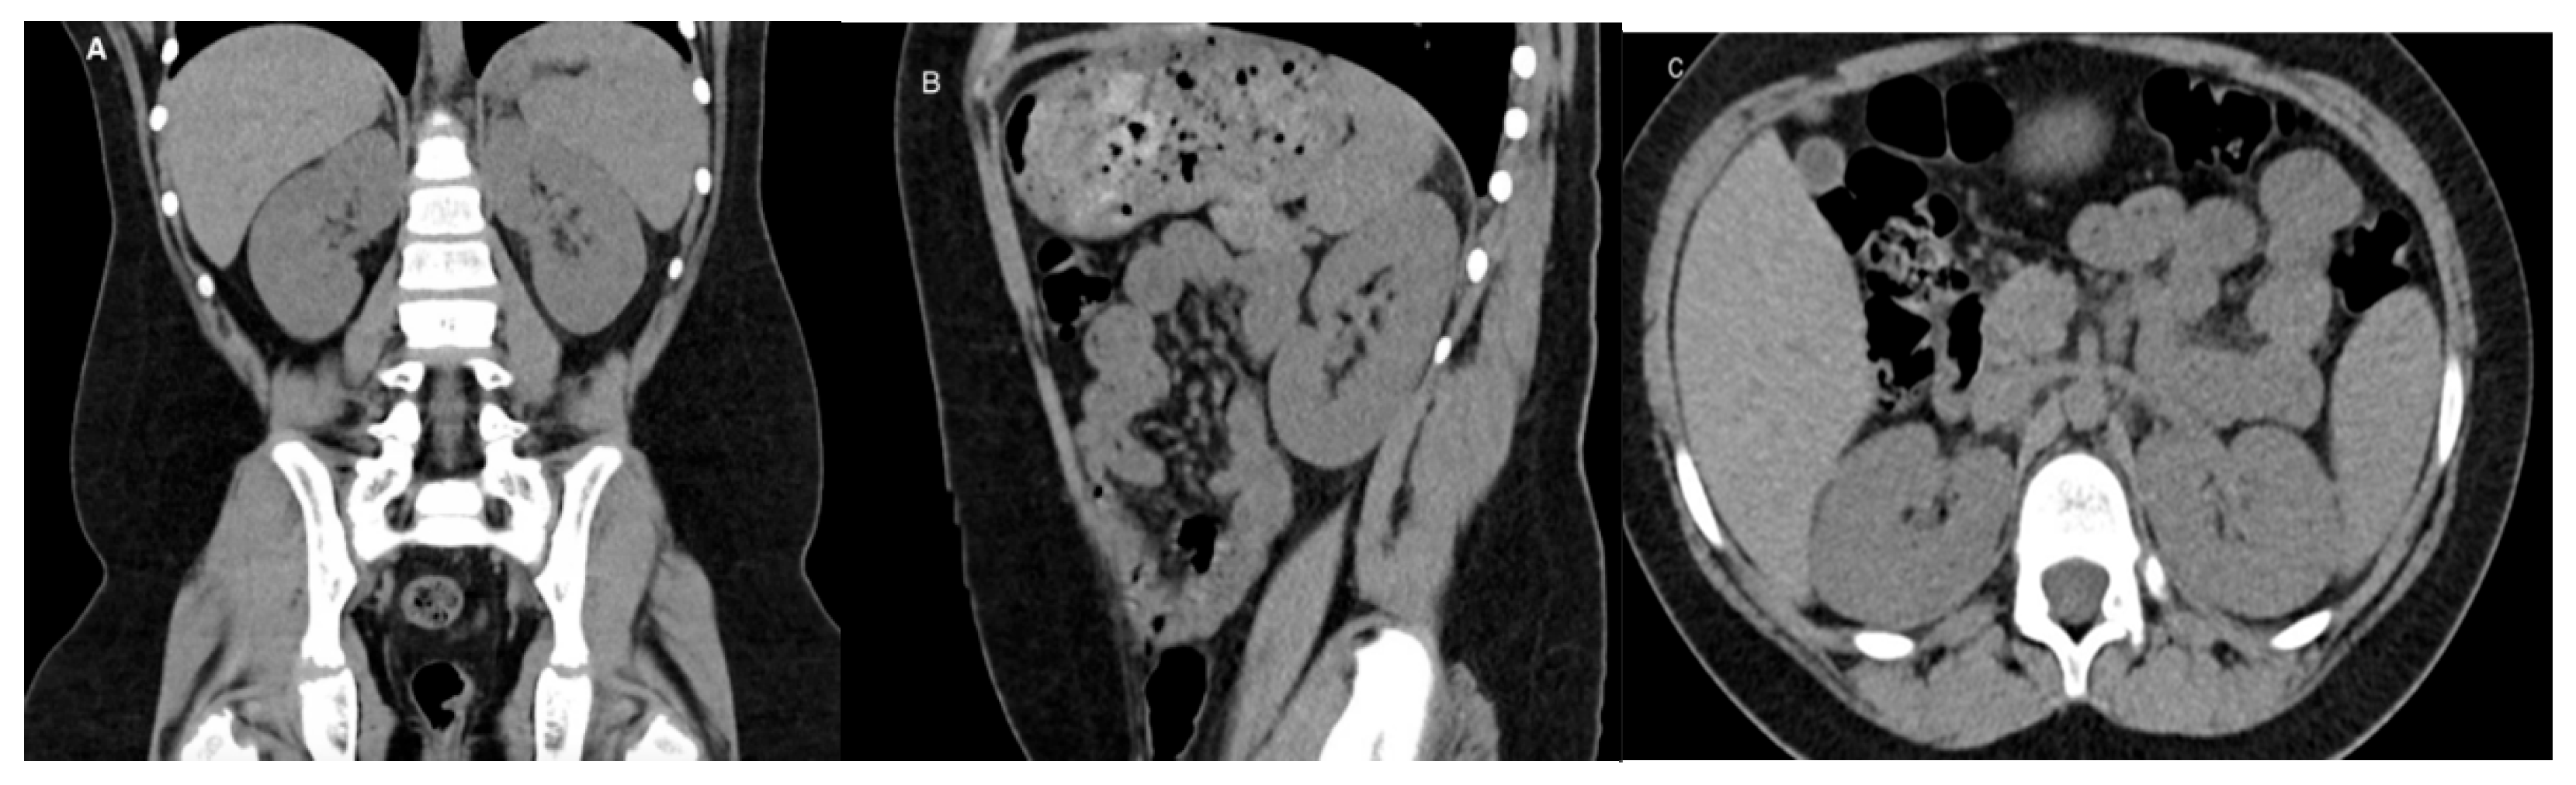

CT is a cross-sectional imaging technique widely used for diagnosing renal diseases in children. It provides high-resolution images of the urinary tract and retroperitoneal structures (Figure 3). However, radiation exposure is a key concern, and to minimize risk, it is recommended to limit the field of view and use weight-based exposure parameters [32,33].

Figure 3. CT of a normal 8-year-old boy: (A) Coronal image, (B) Sagittal image, (C) Axial image.

Medicina 61 00696 g003